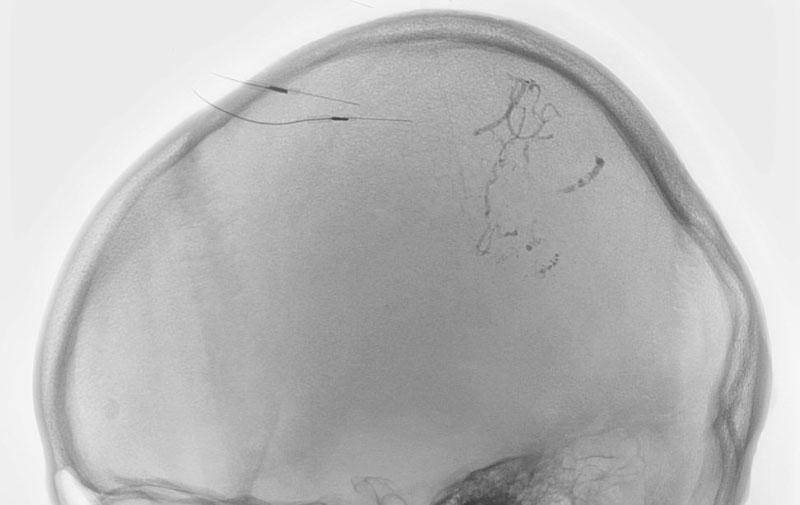

No.1576 手術前

No.1576 手術中

No.1576 手術後

'25年9月

脳動静脈奇形

20代

愛知県の病院